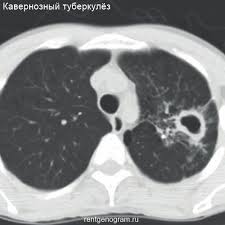

Destruktiw inçekesel görnüşleri. sirrotiki inçekesel

33

1